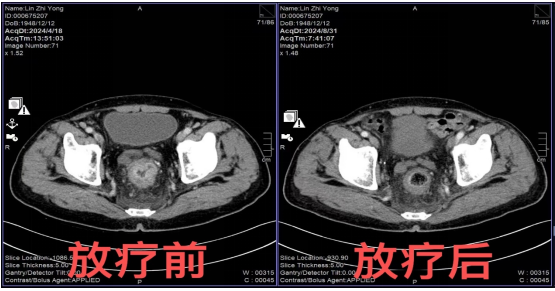

近日,一例76岁老年男性患者,经肠镜及病理活检确诊为直肠腺癌,转入肿瘤中心消化泌尿病区,在肿瘤中心主任医师林思祥的主持下第一时间行多学科MDT讨论,结合目前国内外最新指南最终确定方案为:局晚期直肠癌,分期T3N2aM0,首选新辅助放化疗+TME手术,术后依据病理结果行辅助化疗。患者接受诊疗方案,在我院肿瘤中心消化泌尿病区接受新辅助放化疗(7野调强放疗50Gy/25F,同步卡培他滨口服化疗),放化疗过程顺利、胃肠道及骨髓毒性反应1级,8周后于胃肠外科手术,术后病理回报:肿瘤退缩分级(AJCC)TRG 0级,无癌细胞残留,达到病理完全缓解(pCR)。

科普知识:TRG 0级(病理学完全反应,pCR):没有可见的活癌细胞。TRG 1级(近完全反应):单个细胞或稀少的小团体癌细胞。TRG 2级(部分反应):有残留癌细胞,显示出明显的肿瘤退缩,但超出单个细胞或稀少的小团体。TRG 3级(差或无反应):大量残留癌细胞,无明显肿瘤退缩。该患者取得了T分期(原发灶)和N分期(转移淋巴结)的双重病理完全缓解(pCR)。